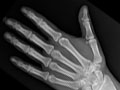

Una radiografía de las extremidades es una imagen de la mano, la muñeca, el brazo, el pie, el tobillo, la rodilla o la pierna. Se realiza para ver si se ha fracturado un hueso o si se ha dislocado una articulación. También se usa para ver si hay una lesión o un daño a causa de afecciones, como infección, artritis, crecimientos óseos (tumores) u otras enfermedades de los huesos como osteoporosis.

Una radiografía de las extremidades es una imagen de la mano, la muñeca, el brazo, el pie, el tobillo, la rodilla o la pierna. Se realiza para ver si se ha fracturado un hueso o si se ha dislocado una articulación. También se usa para ver si hay una lesión o un daño a causa de afecciones, como infección, artritis, crecimientos óseos (tumores) u otras enfermedades de los huesos como osteoporosis. En una emergencia, el médico puede observar los resultados iniciales de una radiografía de las extremidades en algunos minutos. En caso contrario, por lo general, un radiólogo tiene listo el informe oficial de la radiografía el día siguiente.

Los huesos o las articulaciones podrían mostrar señales de daño a causa de una enfermedad, como osteoporosis, artritis reumatoide, osteoartritis, gota o enfermedad de Paget. Vea imágenes de artritis reumatoide en los pies y artritis reumatoide en las manos.  |